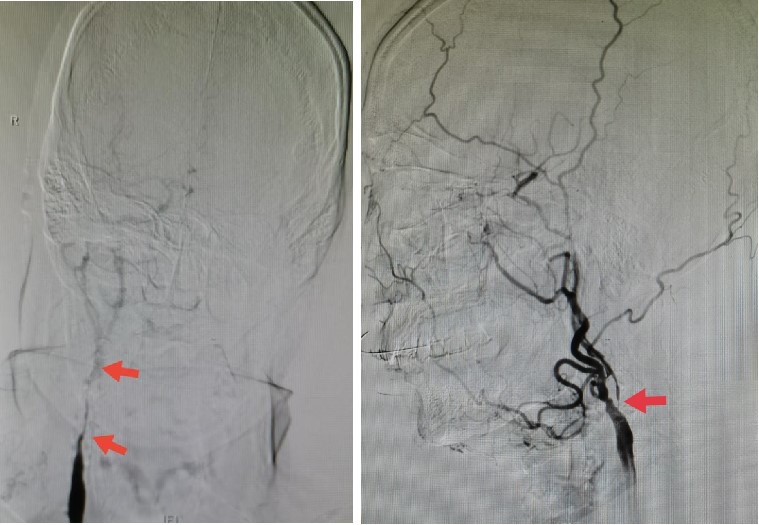

术前脑血管造影:右侧颈动脉长节段99%狭窄近闭塞(左),左侧颈内动脉起始部99%狭窄近闭塞(右)

张小峰(左图)为病人术中复合介入造影,术中造影显示剥脱远端无狭窄,脑血流明显改善(右图)

开放阻断时,请麻醉科降低血压,避免血流过度灌注,在各种监测均显示正常后,神经介入张小峰与沈懿医师行术中复合脑血管造影,“我们确认剥脱术后远端无狭窄,脑血流明显改善,不再需要支架辅助了。”张小峰说,手术顺利结束。